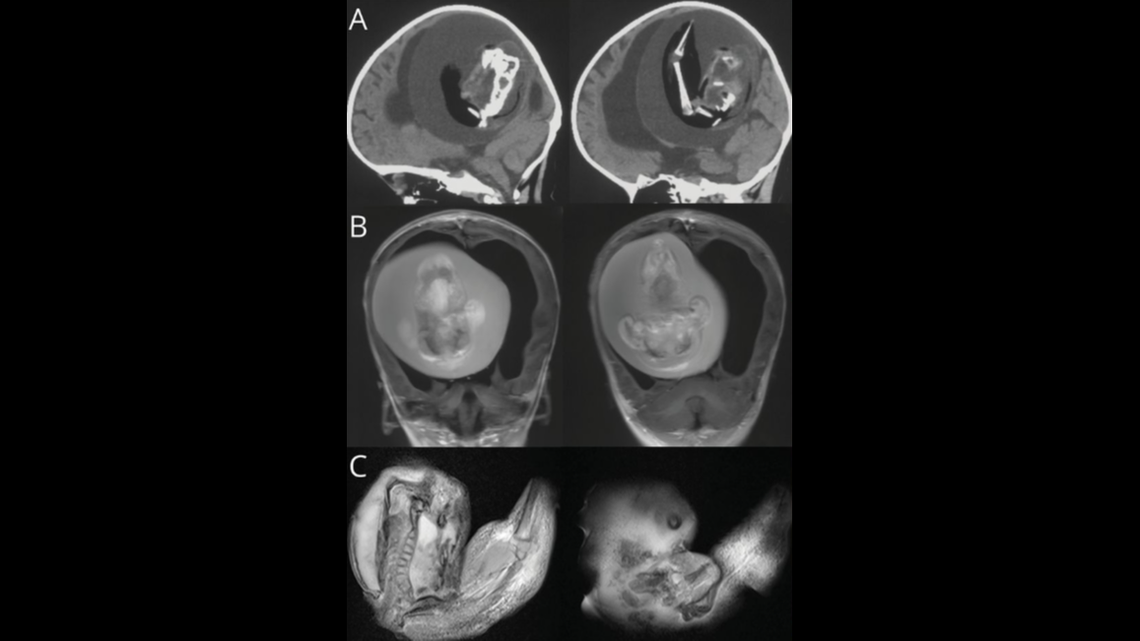

What they removed was a fetus, about 10 centimeters long, with the beginning formations of arms and hands. The fetus had a spine, but remained extremely undeveloped. The doctors called it a “fetiform,” a type of growth that resembles a fetus.

When they ran DNA tests on the growth, they confirmed it was the twin of the living girl that had been absorbed during a developmental process called neural plate folding, a step necessary for the structure of the brain and spinal cord. This would explain how the parasitic fetus ended up inside its sister’s skull.

The parasitic twin was around 10 centimeters long and had arm and hand structures, the doctors said.

The parasitic twin was around 10 centimeters long and had arm and hand structures, the doctors said. Neurology